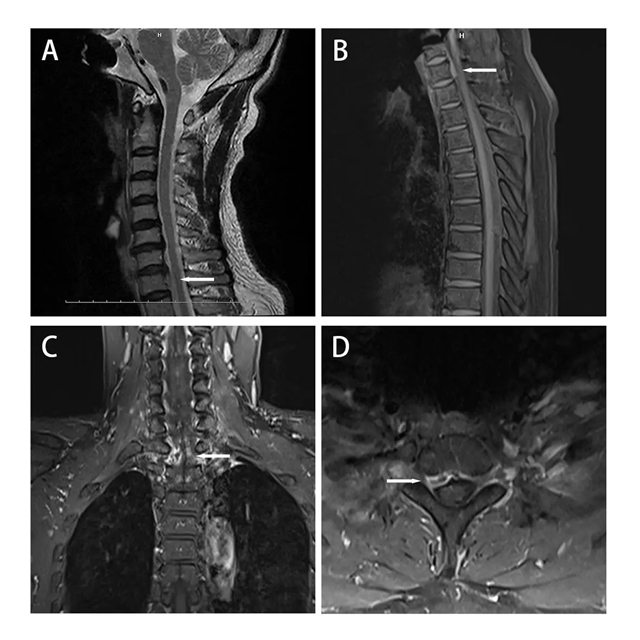

术前MRI表现

别人家的椎间盘突出,一般在脖子中段(C3-C7)搞事情。

而泸州李大哥的椎间盘一路狂奔,直接“位移”到了脖子和胸口的交界处——C7-T1! 这个位置,堪称手术雷区。

为啥叫“雷区”?因为在这个狭小的区域,有给全身供淋巴液的“生命管道”胸导管、掌管发声的喉返神经... 密密麻麻全是重要结构!

如果按照传统手术方案,为了摘这个“炸弹”,可能得开胸劈骨!